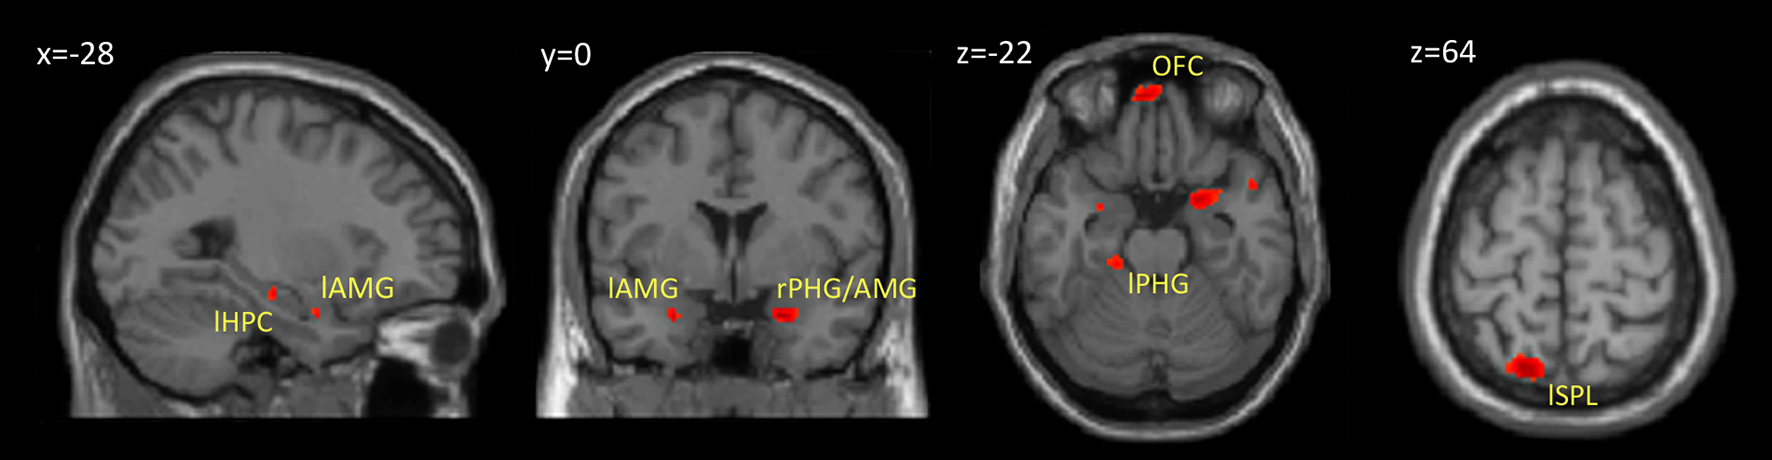

Within our neuroimaging data we found a subsequent memory effect in several limbic and non-limbic areas. Limbic areas included the left hippocampus, bilateral amygdalae, left parahippocampal gyrus, and posterior cingulate gyrus. Activity outside the limbic cortex was found in the posterior cerebellum, left superior parietal lobule, and medial frontal cortex including the rectus gyrus and orbital frontal gyrus. Details are provided in Table 1 and Figure 3.

Figure 3. Brain regions showing a subsequent memory effect. The figure shows the results from contrast between subsequently recognized faces (hits) and subsequently forgotten faces (misses) (p < 0.001, uncorrected). Abbreviations are listed in Table 1.